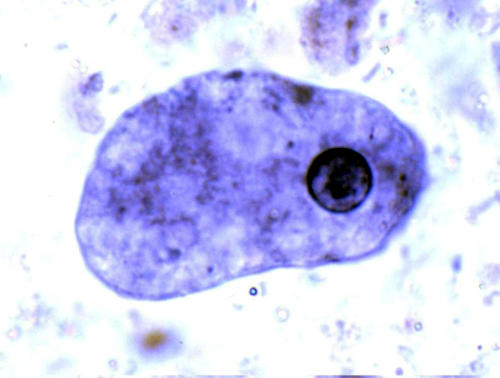

Дизентерийная амёба в анабиозе

Анабиоз (греч. anabiosis — оживление, от ana вновь и bios — жизнь) — выработанная в процессе эволюции приспособительная реакция организмов к крайне неблагоприятным условиям внешней среды. При анабиозе временно резко снижается обмен веществ в живой ткани, но не утрачивается жизнеспособность и специфичность. Поэтому анабиоз определяют как обратимо прерванную жизнедеятельность. Способность организмов длительное время находиться в состоянии анабиоза широко используется в научных исследованиях и на практике. Проведены опыты, в ходе которых с помощью жидкого гелия (–269°C) и жидкого водорода (–253°C) удавалось вводить в состояние анабиоза некоторые микробы и их споры, дрожжевые грибы, семена и пыльцу растений, споры папоротников и мхов, водоросли и др.

Подвергаются анабиозу также амёбы, нематоды и другие черви, тихоходки, яйца и гусеницы насекомых, клетки и ткани амфибий и другие. Некоторые ткани (например, кровь) сохраняют способность переносить длительное и глубокое охлаждение без потери жизнеспособности при добавлении таких защитных веществ, как глюкоза, этиленгликоль, глицерин и других. Сперма животных после глубокого охлаждения жидким водородом сохраняет способность к оплодотворению.

У некоторых организмов анабиоз входит в нормальный цикл развития (семена, споры, цисты).